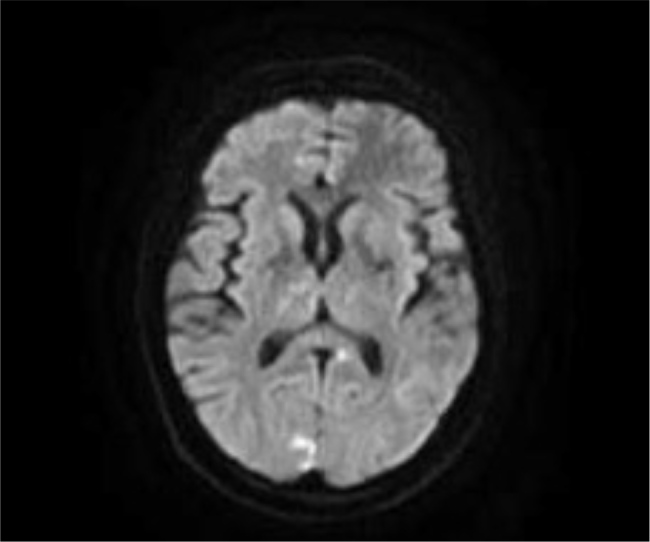

Case description: A 45-year-old female with diabetes, hypertension and multiple ischaemic strokes presented with altered consciousness due to hypoglycaemia. Initial workup at a different hospital suggested cerebral vasculitis based on the findings of cerebral angiography. She had negative systemic vasculitis markers and was treated with corticosteroids and rituximab and discharged. On admission to our facility, an MRI of the brain revealed multiple infarcts of varying ages, and a CTA showed arterial beading, suggestive of primary CNS vasculitis. CSF analysis demonstrated elevated protein and IgG without pleocytosis. Despite high-dose corticosteroids and rituximab, she developed progressive neurological deterioration with new infarcts in the vertebrobasilar territory, leading to brainstem dysfunction and brain death.

Learning points: Physicians should be alert in diagnosing primary CNS vasculitis in a young patient with recurrent strokes affecting multiple vascular territories, particularly when systemic vasculitis markers are negative.Imaging studies, such as MRI and computed tomography angiography (CTA), play an essential role in diagnosing primary CNS vasculitis, with findings such as arterial beading and a multi-infarct pattern helping differentiate it from atherosclerotic diseases.Early recognition and aggressive high-dose corticosteroid and immunosuppressive (rituximab) therapy are essential in primary CNS vasculitis, as delayed treatment can result in rapid neurological deterioration, as seen in this case.